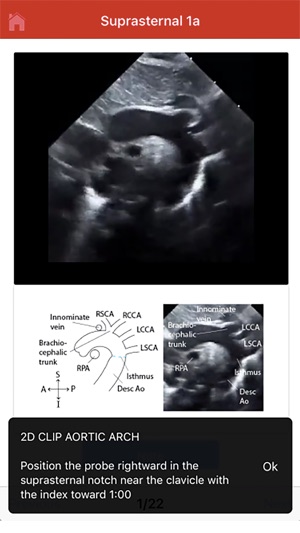

This educational tool, developed in connection with the University of Wisconsin-Madison, provides procedural guidance for performing a normal pediatric echocardiogram. The system delivers instructional content organized by four standard imaging views: subcostal, parasternal, apical, and suprasternal. To facilitate skill acquisition, the platform integrates multimedia assets, including video clips, static images, and technical illustrations. A user can navigate through a protocol sequentially or access specific views directly. Procedural instructions are displayed automatically upon view selection and can be supplemented with additional notes accessible through the interface.